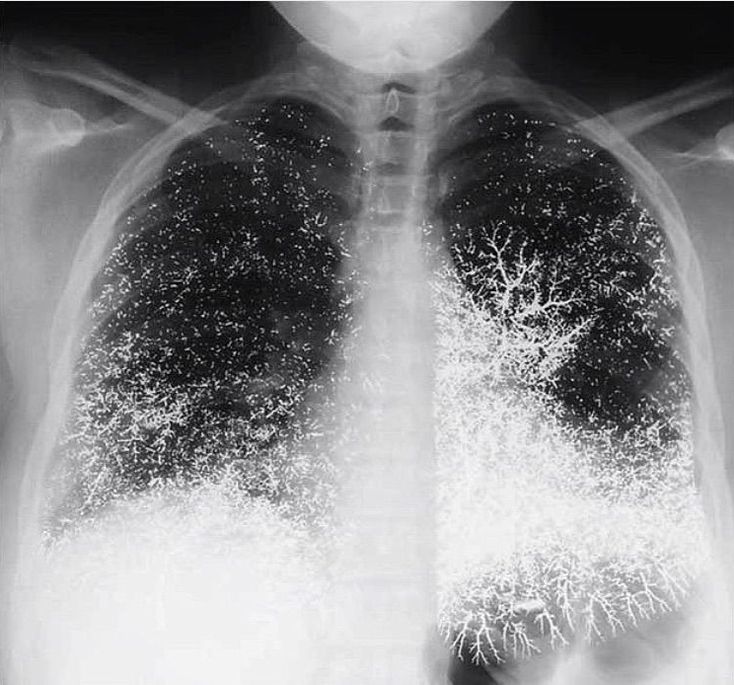

Mercury embolism to the lungs!! A 21-year-old dental assistant attempted suicide by injecting 10 ml (135 g) of elemental mercury intravenously. She presented to the emergency room with tachypnea, a dry cough, and bloody sputum. A chest radiograph showed that the mercury was distributed in the lungs in a vascular pattern that was more pronounced at the bases. The patient was discharged after one week, with improvement in her pulmonary symptoms. Oral chelation therapy with dimercaprol was given for nine months, until the patient stopped the treatment; the urinary mercury level did not change during this period. At follow-up at 10 months, she was healthy, with none of the renal, gastrointestinal, or neurologic effects that can result from the oxidation of mercury in the blood and consequent exposure of these organ systems. The abnormalities on the chest radiograph were still apparent. Although these abnormalities are striking, the absence of clinical toxicity in this patient illustrates the differences in the acute and chronic effects of exposure to elemental mercury, inorganic mercury (e.g., mercuric chloride), and organic mercury (e.g., dimethylmercury). Inorganic and organic mercury are much more toxic than elemental mercury; for example, a dose of 400 mg of mercury in the form of dimethylmercury is usually lethal.